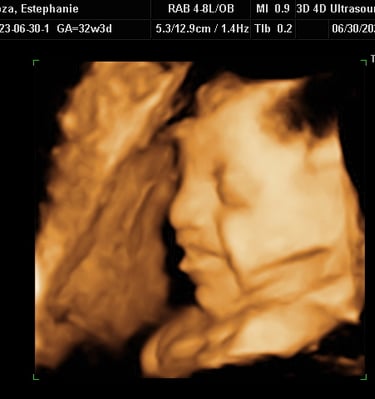

Our Gallery

Explore beautiful moments captured during our 3D and 4D sessions.